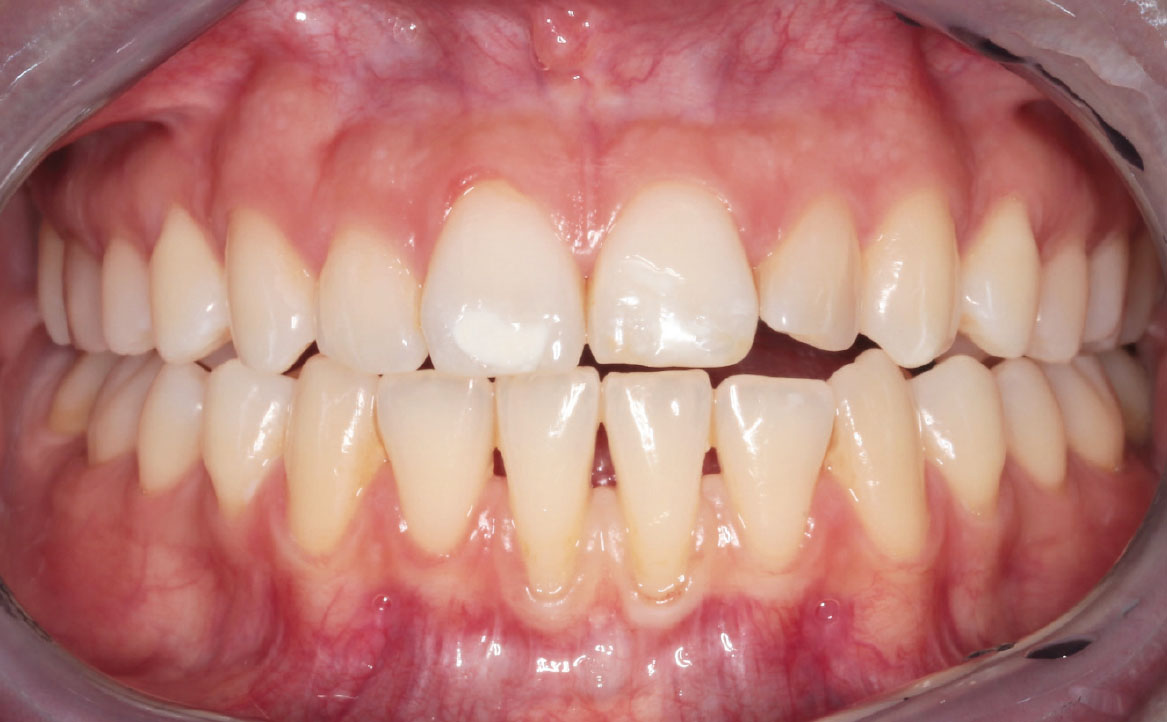

Al follow-up a un mese dalla vestibuloplastica, si osserva la completa riepitelizzazione del sito chirurgico (fig. 13, 14). Si riscontra la presenza di una piccola area esofitica, dovuta al mancato riassorbimento di uno dei punti di sutura applicati.